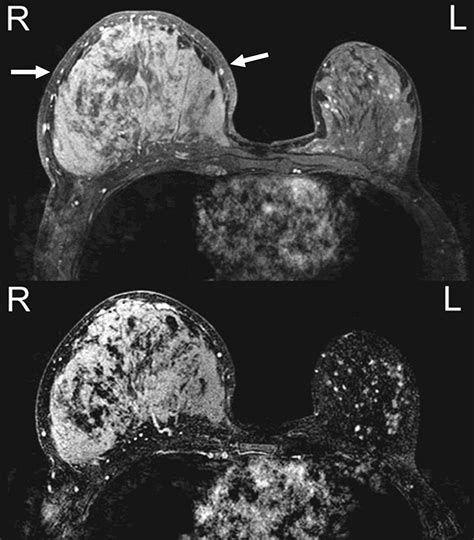

Magnetic Resonance Imaging (MRI)

MRI provides high-resolution images of the breast tissue, offering a more comprehensive view of the affected area. MRI is especially effective in detecting the extent of inflammation and identifying any underlying tumors. This makes MRI a crucial tool for capturing detailed Pictures Of Ibc Breast.